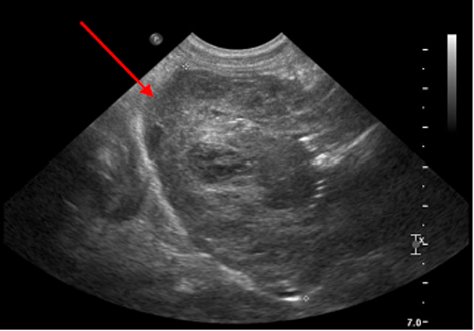

Echographie Réno-vésicale

Egalement appelée échographie des reins et de la vessie, c’est une procédure d’imagerie qui permet d’evaluer la santé des reins et de la vessie, ainsi que pour diagnostiquer diverses affections et problémes médicaux liés à ces organes.